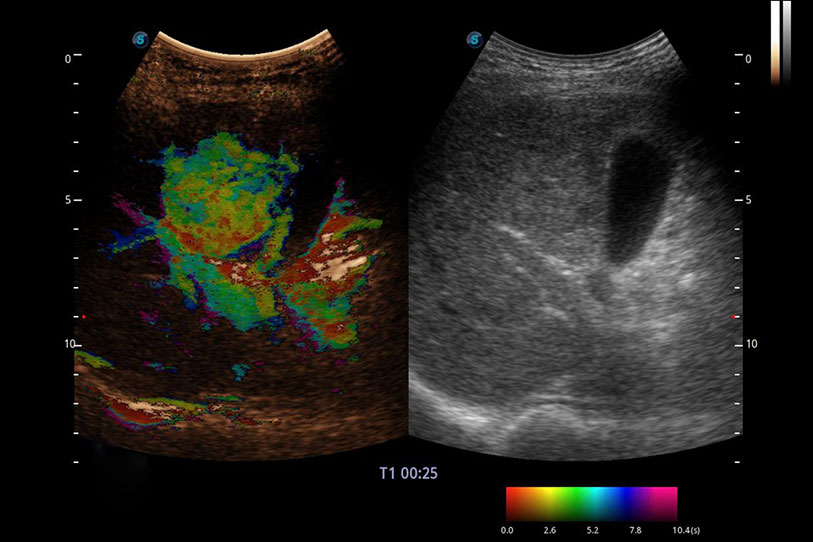

采用紅、橙、黃、綠、青、藍(lán)、紫這七種肉眼最為敏感的色彩,直觀地顯示組織內(nèi)血流灌注的時間先后信息,更精準(zhǔn)捕捉血流灌注走行細(xì)節(jié)。